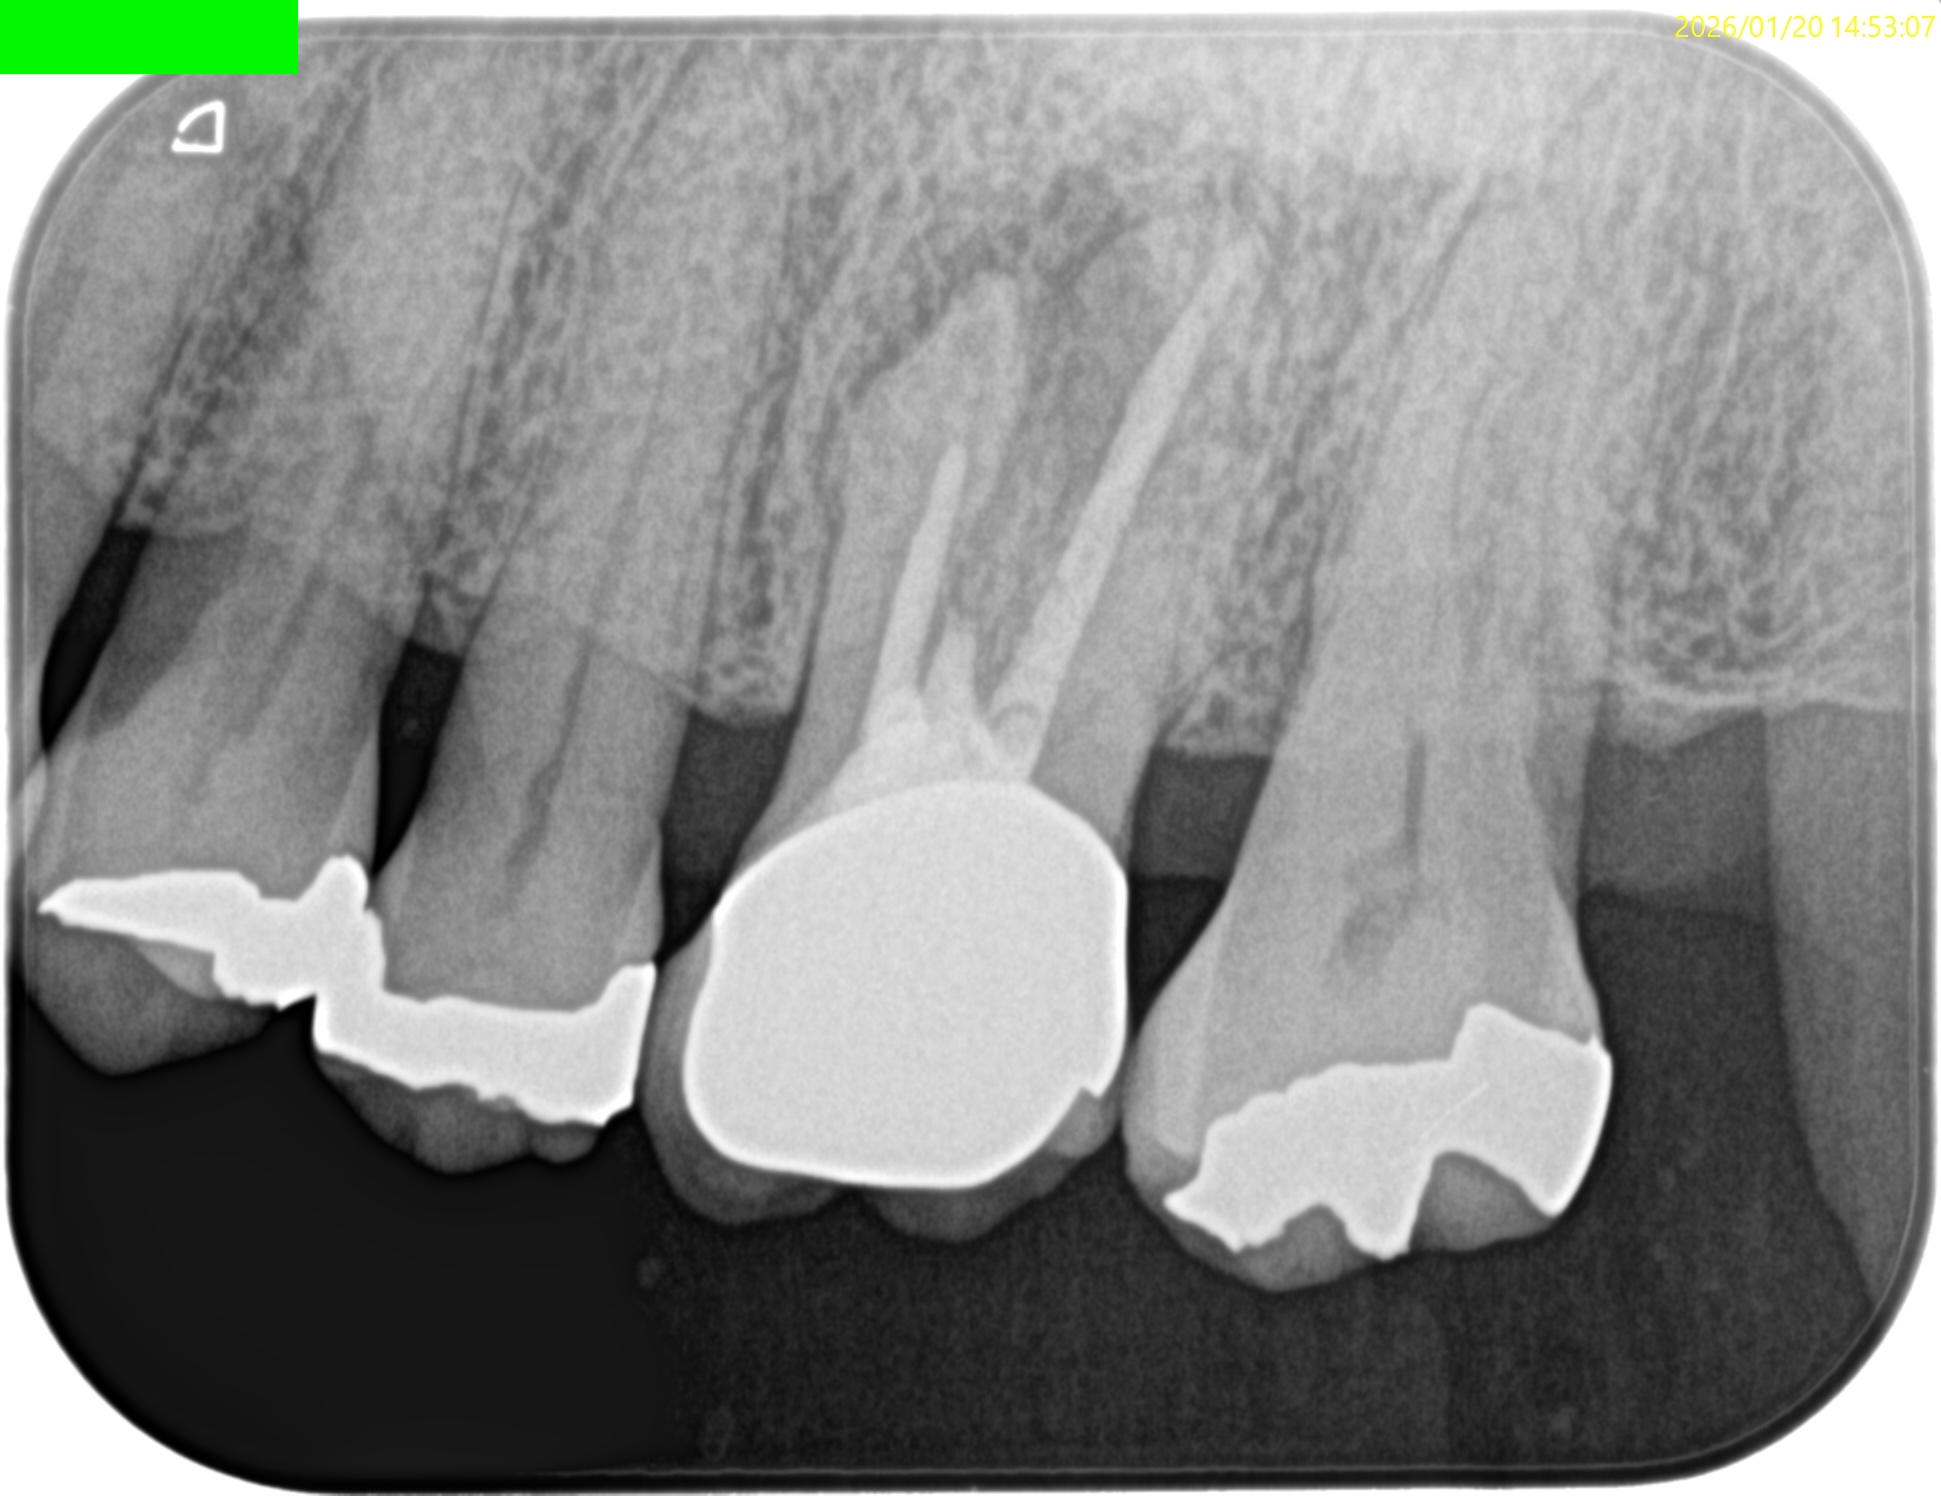

MB

DB

P

MB,DBは石灰化が進み再根管治療で穿通は不可能であろう。

故にここはApicoectomyだ。

が、P根は

作業長が16~18mm程度であるが

Apical Foramenまで根管充填できていないし、シーラーパフもない。

さておき、この同意書のPAではMB,DB,Pに根尖病変があるように見える。